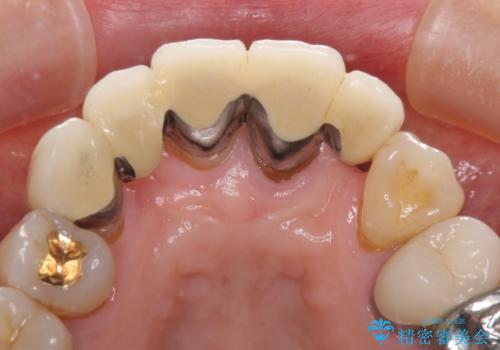

- ブリッジと歯肉の隙間にものが挟まったり空気が抜けたり、歯肉ラインの黒い縁が目立ってしまったりと、前歯のブリッジの作り直しを希望して来院された患者様です。

自然な仕上がりとするため、金属を使用しないオールセラミックブリッジにより補綴治療を行うこととしました。